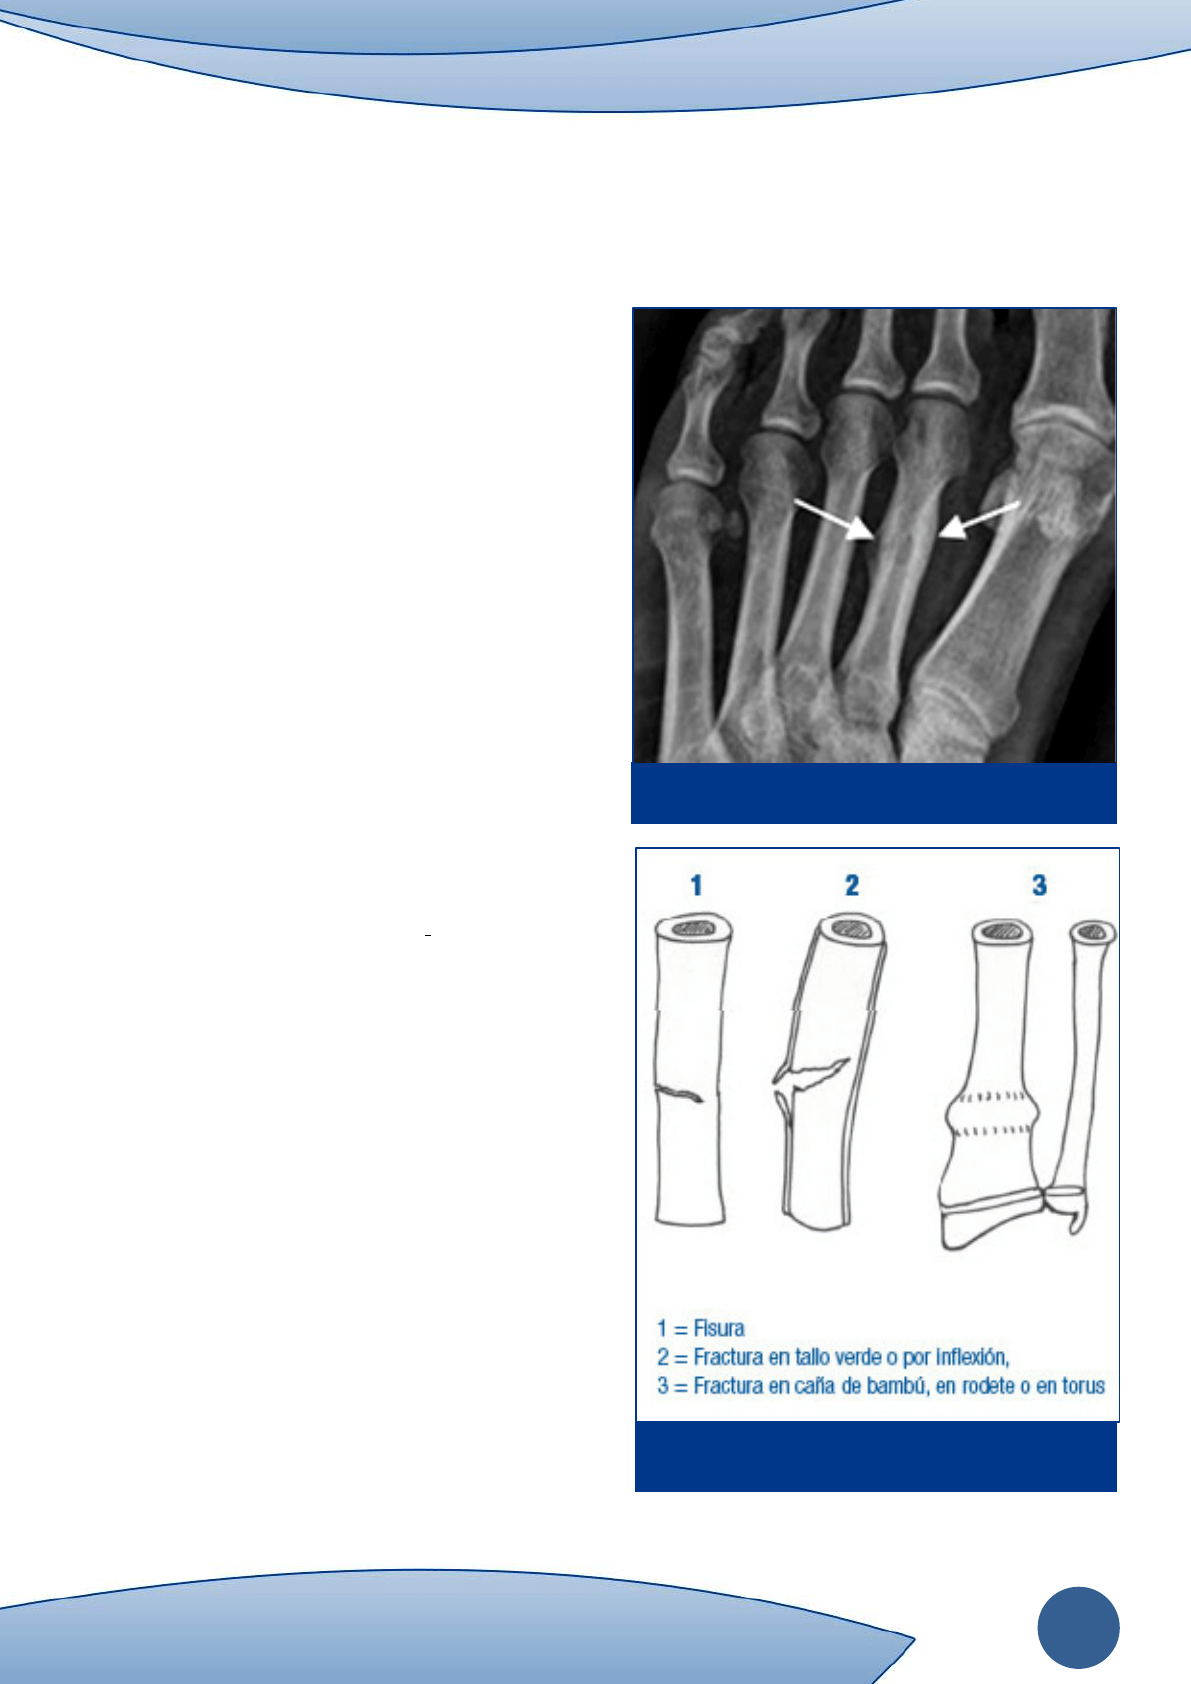

Figura 7.